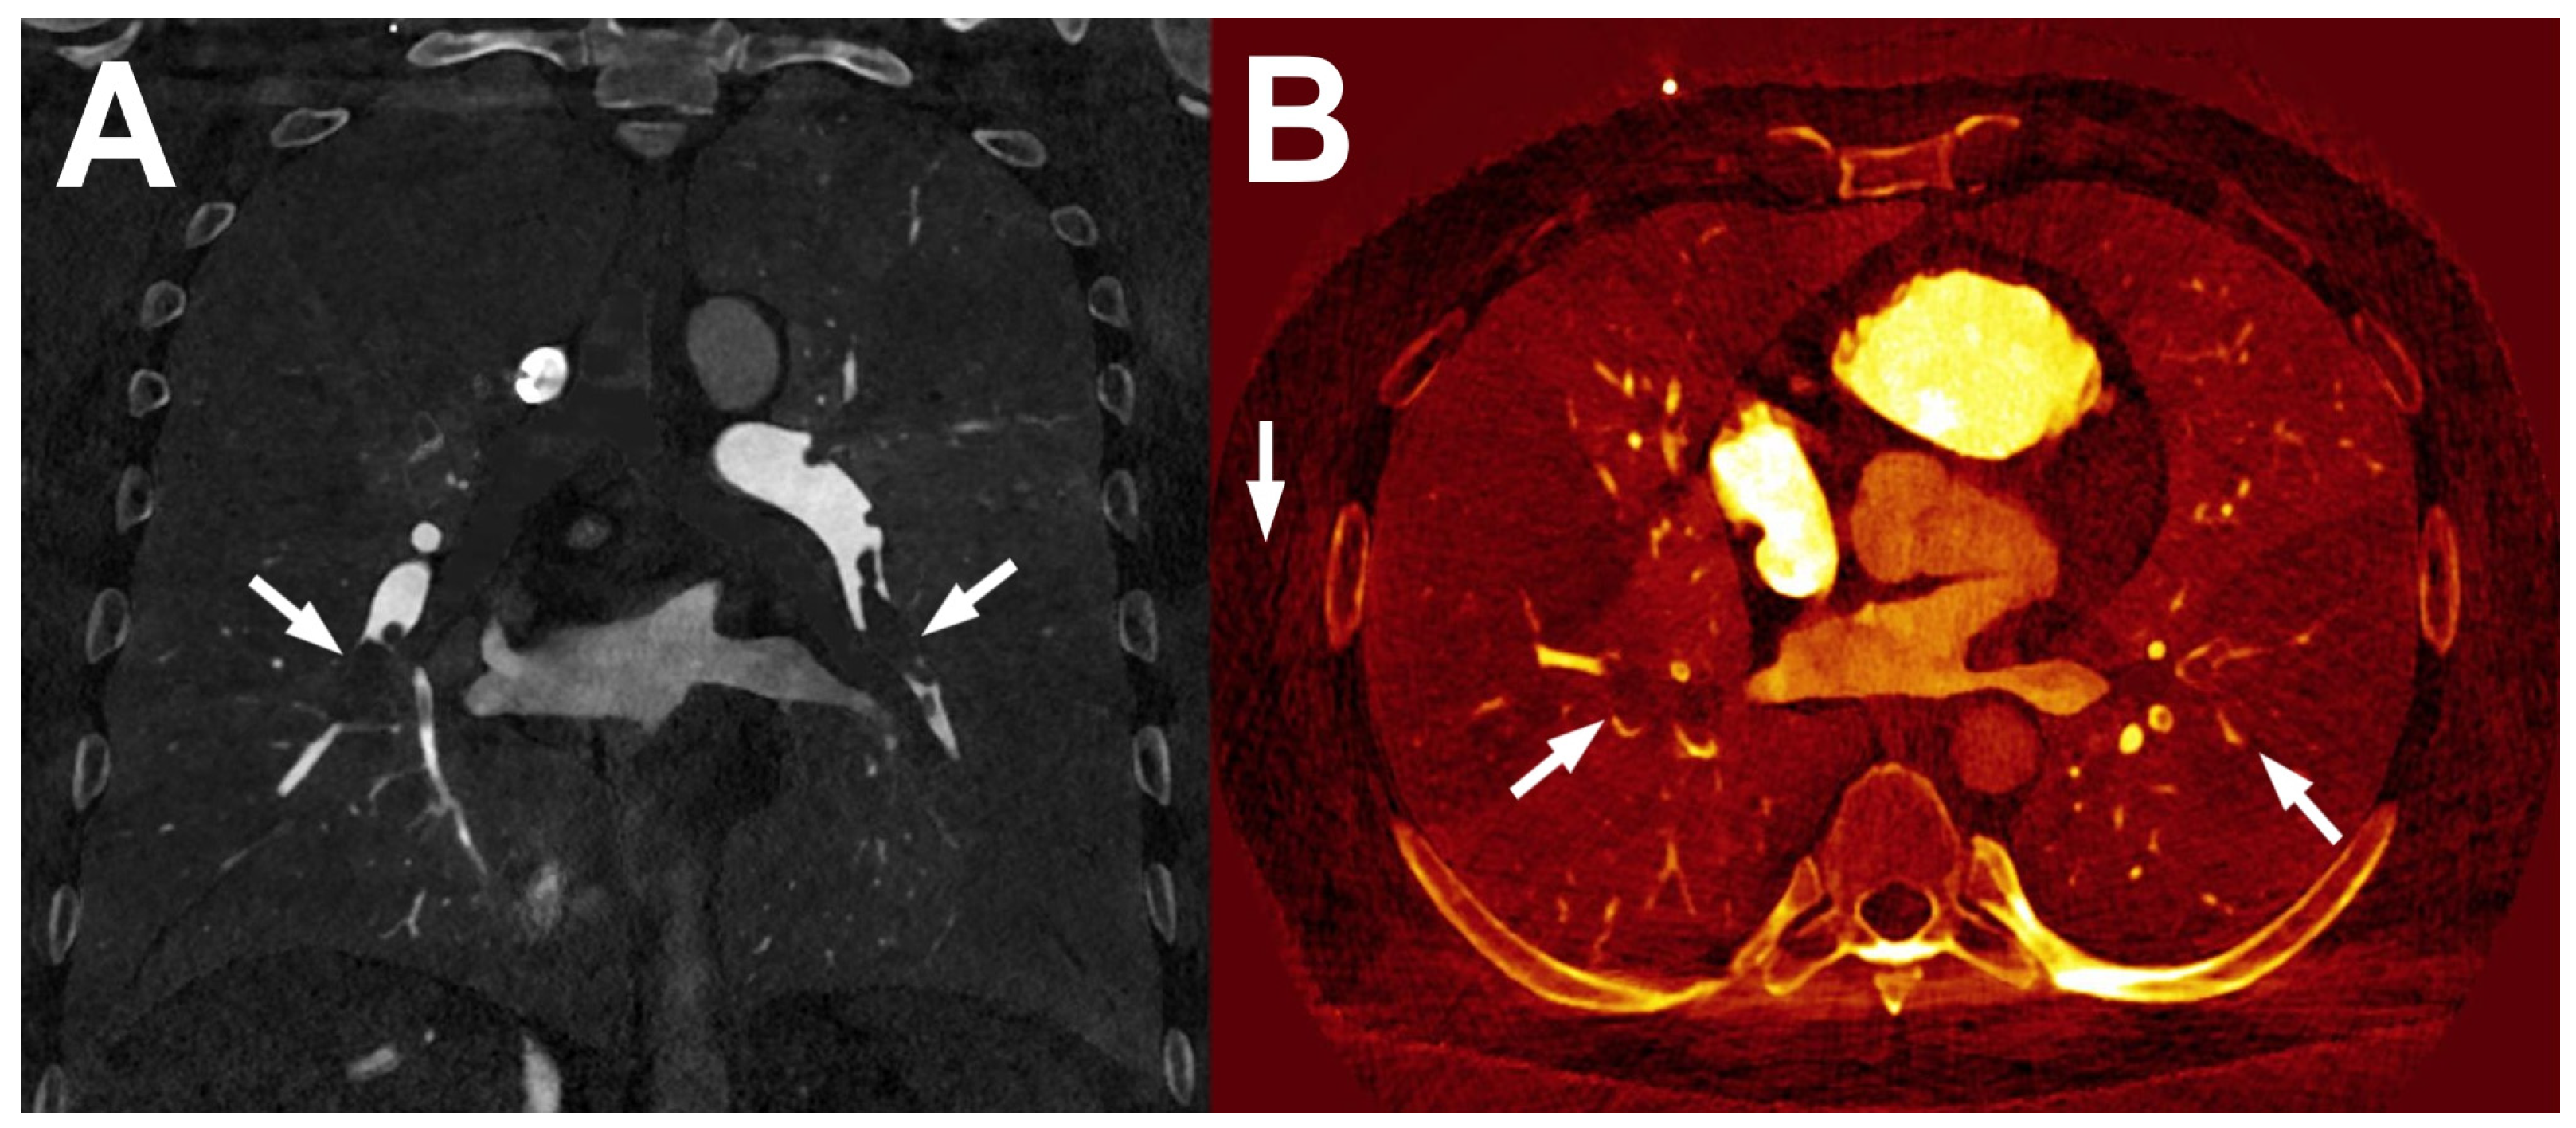

- Kazimierczak, W.; Kazimierczak, N.; Lemanowicz, A.; Nowak, E.; Migdalski, A.; Jawien, A.; Jankowski, T.; Serafin, Z. Improved Detection of Endoleaks in Virtual Monoenergetic Images in Dual-Energy CT Angiography Following EVAR. Acad. Radiol. 2023, 30, 2813–2824. [Google Scholar] [CrossRef] [PubMed]

- Kazimierczak, W.; Kazimierczak, N.; Wilamowska, J.; Wojtowicz, O.; Nowak, E.; Serafin, Z. Enhanced Visualization in Endoleak Detection through Iterative and AI-Noise Optimized Spectral Reconstructions. Sci. Rep. 2024, 14, 3845. [Google Scholar] [CrossRef] [PubMed]